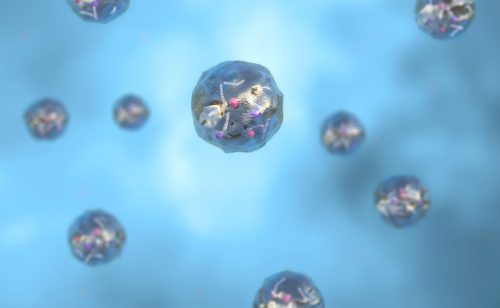

Exosome Therapy as a Potential Alternative to Surgery

Joint pain is usually due to decreased joint fluid or loss of strength of the cartilage tissue. Traditional treatments for joint pain include medication, physical therapy, and surgery – however, these have side effects, are invasive, and require lengthy recoveries. Fortunately, there is now an emerging alternative: exosome therapy.